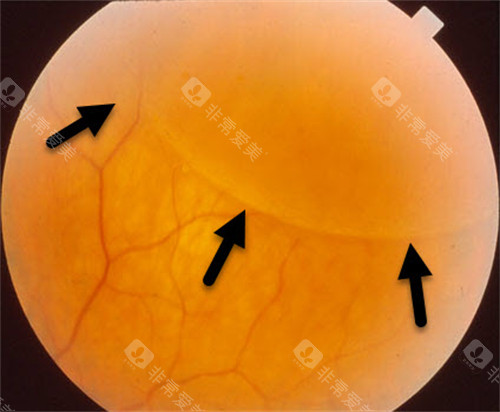

45岁糖尿病患者王先生,因视力骤降就诊,确诊为增殖性糖尿病视网膜病变伴玻璃体出血。

孙医生为其多期实施玻璃体切割手术联合全视网膜光凝,术后6个月视力从0.1修复至0.6。

类似实例中,80%患者术后视力得到显著改善,并发症发生率低于5%。

临床数据显示,孙医生主刀的视网膜复位手术成功几率达92.3%,其中:

原发性视网膜脱离患者术后视力改善率85%

高度近视黄斑裂孔闭合率89%